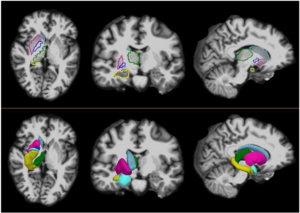

The regions-of-interest (ROIs) were manually drawn by an experienced radiologist by using the b 1000 images, averaged for all measured directions, the FA maps and the proton-density weighted images. For that purpose, the maps of ADC, FA, R2 and R2* as well as the proton-density weighted images were first co-registered. The ROIs were segmented by syncing the b 1000 images, averaged for all measured directions, the FA maps and the proton-density weighted images in ImageJ. The ROIs were stored in the ROI manager and transferred to the co-registered maps. The segmented brain regions were highlighted in different colors: CN—black; PU—red; GP—green; TH—white; SN—blue; CC—cyan. The diffusion-weighted images, the R2 and R2*-weighted maps were transferred to the 3D Slicer software in order to co-register the R2 and the R2* maps as well as the MD and the FA maps |

MRI with labeled structures from atlas registered to the CBCT. Registration was carried out with the open source imaging tool 3D Slicer, Version 4.4.0. |

Example of (A) a GS 6(3+3) tumor and (B) a GS 9(4+5) tumor. The top row shows the ADC image with the computed energy and entropy values overlaid on the tumor. The bottom row shows the T2-w MR image with the computed energy and entropy values overlaid on the same tumor on the corresponding slice. The texture features were computed per voxel by using a 5×5×5 patch centered at each voxel. Tumors and normal structures were identified and volumetrically segmented on both the T2-w and ADC MR images using 3D Slicer. |